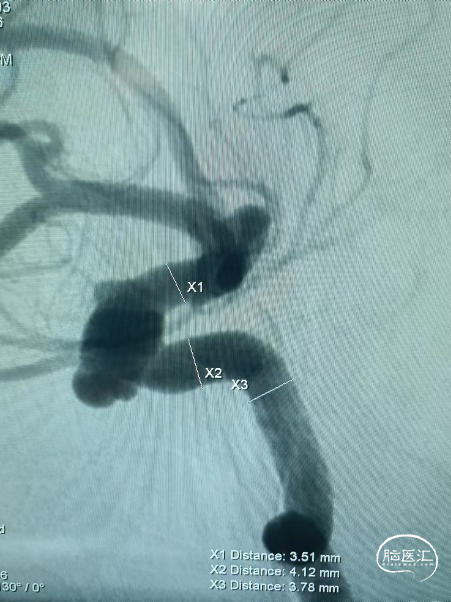

3、多体位造影,确认支架头端没有覆盖脉前动脉。

术后正位造影